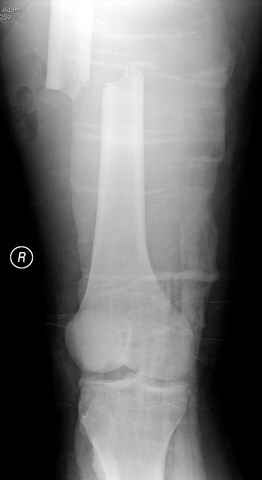

03.14.2005

больному 42, автоавария, политравма, открытая черепномозговая травма, безсознании, открытый перелом бедра, размозжение мягких тканей, дефект кожи на передней поверхности бедра около 13 см2 от ожога, компартмент синдром.

По поводу открытого перелома больной ургентно взят на ретроградное интрамедулярное штифтование, после рутинного дебрайдмента и фасциотомии на бедре и на голени.

перелом бедра

постоперационные